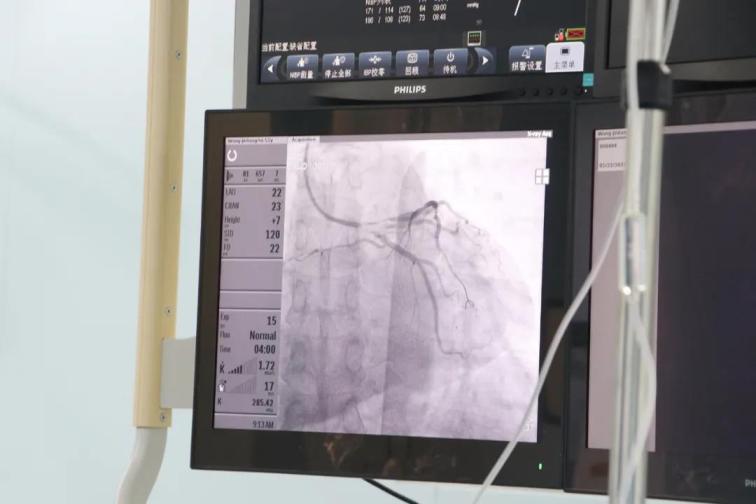

患者王某,男性,52歲,因胸悶半年,加重伴呼吸困難6天于5月8日入院,否認高血壓和糖尿病史,外院256排CT提示:左前降支近段局限性中度狹窄,不能完全排除重度可能。入院后行心臟冠狀動脈造影檢查,結(jié)果提示前降支近段狹窄90%,中段狹窄70%,合并心肌橋,遠段狹窄80%,患者及家屬不接受植入支架,在給予前降支近段充分預(yù)處理后,使用藥物涂層球囊送至病變部位,緩慢加壓,持續(xù)擴張45秒,術(shù)后患者癥狀消失,并于5月27日痊愈出院。